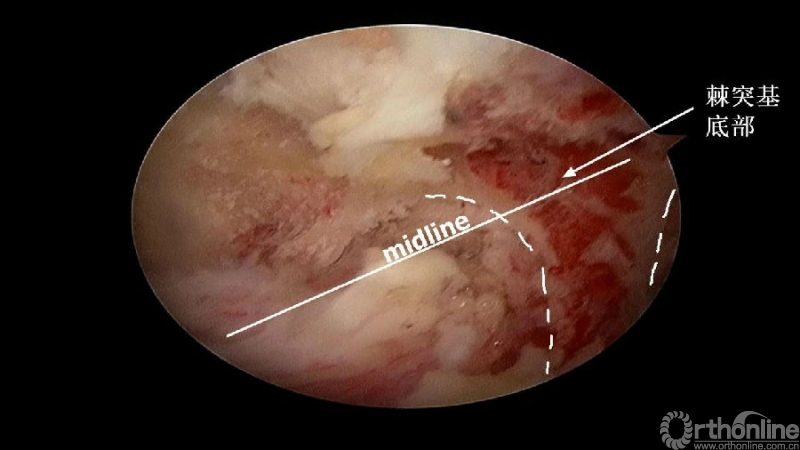

临床上,0°镜子绝对是颈椎UBE的最好用的镜子,但是30°的镜子对侧中线结构的显露及对侧结构的显露具有更广角的视野。在进行同侧减压之前,中线结构的显露是关键。

1. 术中如何确定中线?

2. 术中骨赘的界限?

3. 如何确定对侧结构?